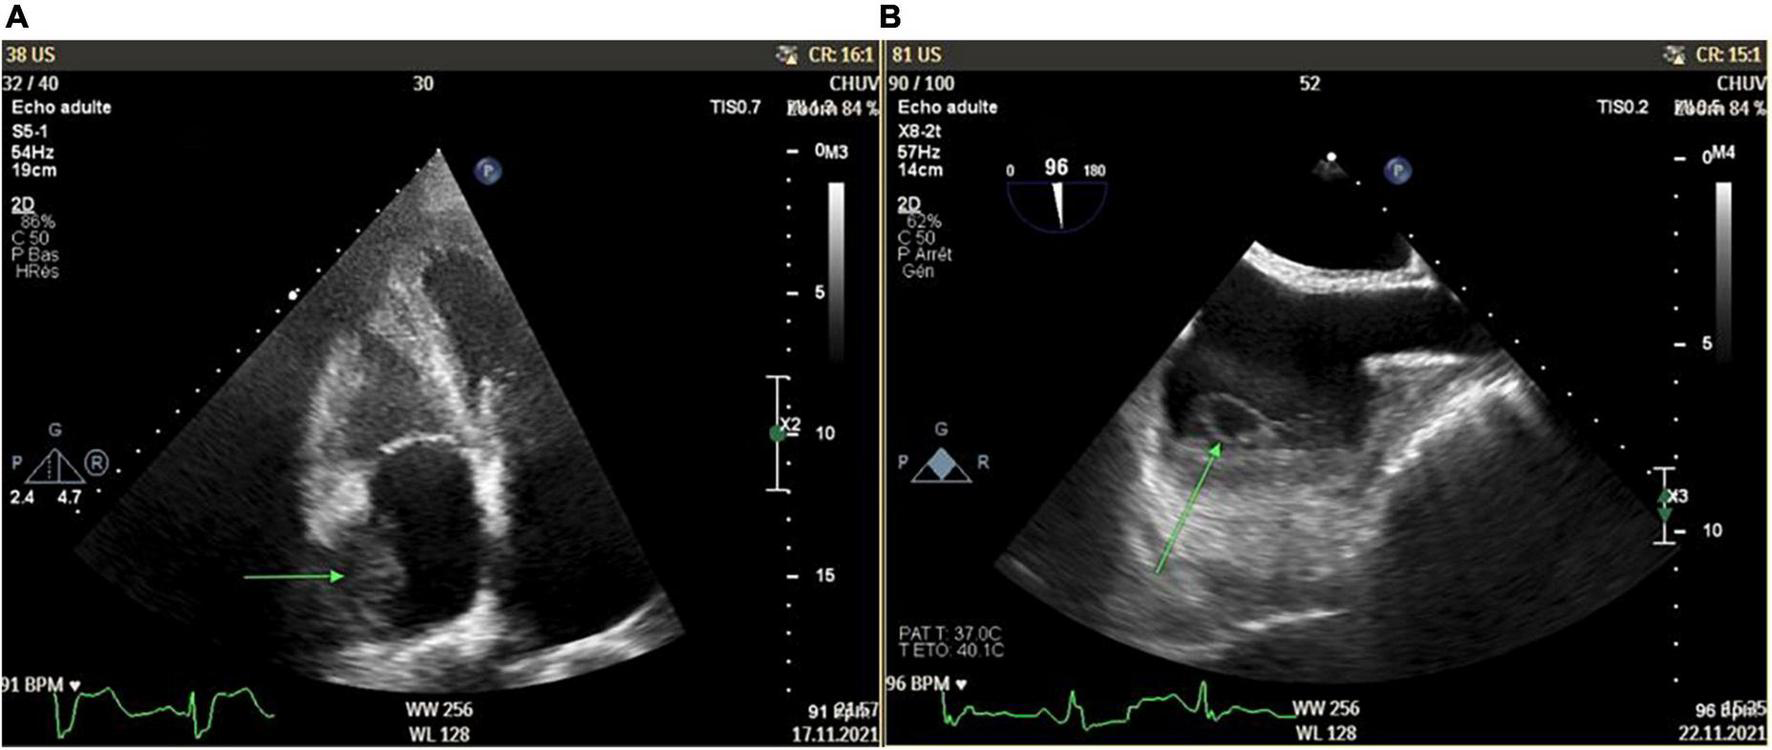

The cardiac workup included a transthoracic echocardiography revealing an atrial mass measuring 15 × 18 mm, with a thickened lateral wall without associated tricuspid valve anomalies (Figure 2A). These findings were confirmed with transoesophageal echocardiography, which showed an abscessed pattern in this mass and moving filaments (Figure 2B). The fundoscopy revealed bilateral endogenous endophthalmitis and Roth spots. Laboratory tests showed increased inflammatory parameters (CRP: 163 mg/L, procalcitonin: 0.66 mcg/L), with relatively low leucocyte count (4.8 G/L) and a KDIGO 1 acute kidney injury. Blood cultures were collected. In order to characterize the nature of the right atrial mass, a whole-body [18F]FDG PET/CT after 24 h of dietary preparation and heparin pre-administration to suppress the physiological myocardial FDG uptake was performed (10). It showed an intense FDG accumulation of the right atrial mass with extension to the epicardium, which was suggestive of an active infectious process. Septic emboli in the lungs, muscles, and subcutaneous tissue were also evident (Figure 3). Brain magnetic resonance imaging (MRI) also highlighted multiple brain lesions.

FIGURE 2

Right atrium mass (15 × 18 mm) with thickened lateral wall without associated tricuspid valve anomalies as shown in transthoracic echocardiography [green arrow, Panel (A)] and transesophageal echocardiography [green arrow, Panel (B)].